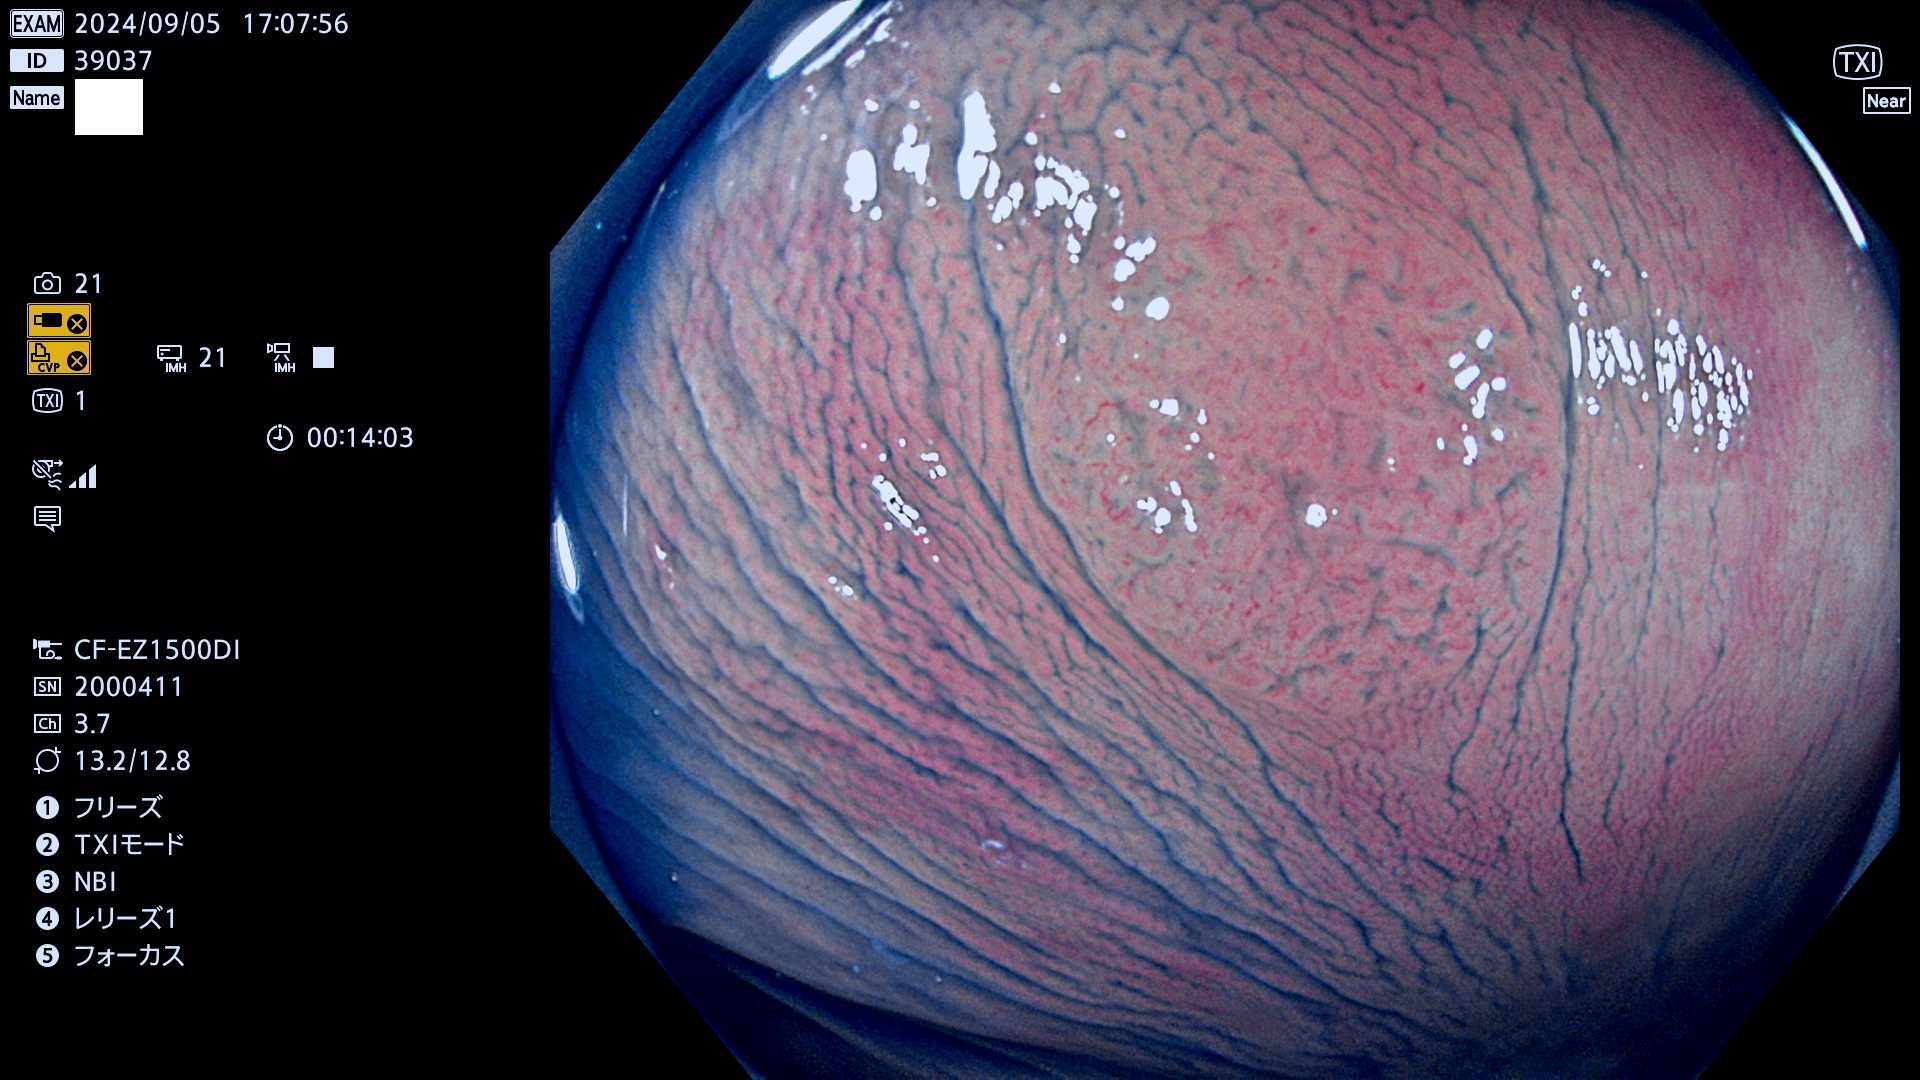

完全に平坦な物をUb、陥凹している物をUcと呼びます。最も発見が難しく危険な病変です。

抽出の対象期間 2024年9月5日〜9月8日の4日間(40件の検査)4件 (4/40=10%)